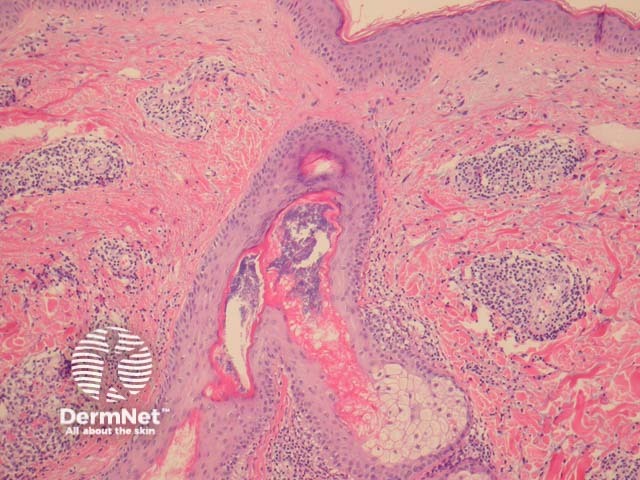

In REM, sections show a superficial and deep perivascular and periadnexal mononuclear infiltrate (figure 1). The epidermis is uninvolved. The presence of copious mucin between collagen fibres of the dermis is characteristic of the disorder (figures 2, 3).

Figure 1